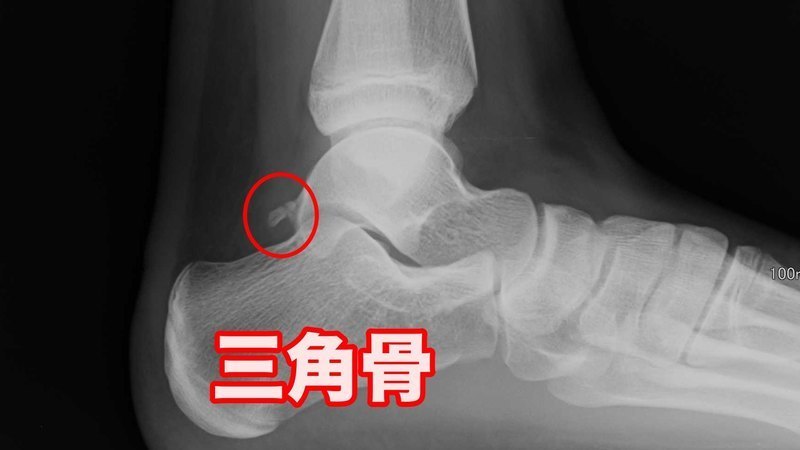

アキレス腱炎と間違われやすい三角骨障害

アキレス腱の奥にある過剰骨

アキレス腱の奥に過剰骨を持つ人が10人に1人の確率でおられます。これを三角骨といい、通常これがあっても問題にはなりませんが、バレリーナやサッカー選手、水泳選手などが足首の過剰な底屈(つま先立ち)を繰り返し、この三角骨が脛骨(すねの骨)と踵骨に挟まれ、まわりの組織に炎症をきたし、痛みを起こす事があります。

当院の整体治療で、三角骨障害も対応可能ですので、ご相談ください。